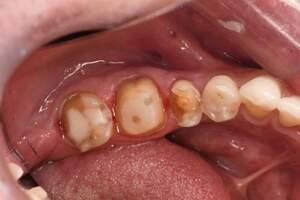

銀歯の中身の写真

麻布十番の歯医者さんで銀歯を外す前の症例写真

麻布十番の歯医者さんで銀歯を外す後の症例写真

こちらは銀歯を外す前と後の写真の比較になります。黒い部分が虫歯になっています。銀歯をつけているとなかなかレントゲンにも虫歯として映ってこないことが多いので、発見が遅れてしまうことがあります。